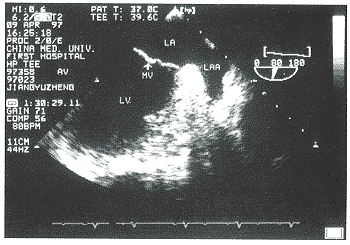

12例左心耳或左心耳和左房血栓患者均显示左心耳内或左房壁有附加血栓回声。其中多块血栓10例,单块血栓2例,最大血栓块面积17.9cm2,最小为0.62cm2。图1为血栓组患者(左图)和非血栓组患者(右图)的左心耳切面超声图像。左图中可见左心耳盲端充满强弱不等的附加回声,术后证实为血栓。右图左心耳轮廓清晰,无附加回声。

左图中可见左心耳盲端充满强弱不等的附加回声(TH)。

LA=左房,LAA=左心耳,LV=左室,LUPV=左上肺静脉,TH=血栓

图1 血栓组患者(左图)和无血栓组患者(右图)的左心耳切面超声图像